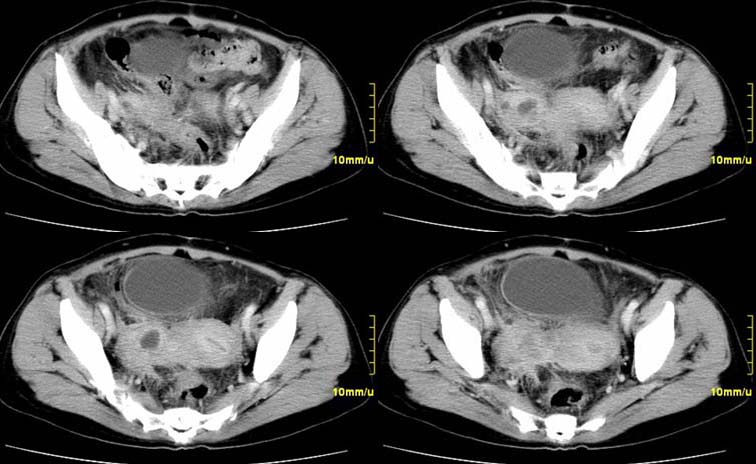

患者,52,右下腹疼痛一月,当时有发热,抗炎治疗20余天,至今仍疼痛,且有低热。

增强

右附件区软组织包块,内囊变坏死,边缘模糊,与子宫,与膀胱分界不清,增强强化与子宫密度相近.盆腔内无肿大淋巴结考虑炎性包块可能性大。

右附件区软组织包块,内可见坏死,边界不清,周围软组织及脂肪组织可见密度增高,膀胱右侧壁增厚,并且呈膨胀不全的改变,考虑炎性包裹,不知道有没有手术史??

临床特点:

右下腹疼痛一月,当时有发热,抗炎治疗20余天,至今仍疼痛,且有低热,具有典型炎症的临床表现。

ct表现:

右侧附件见一肿块,边缘与周围组织分界不清,增强扫描见肿块明显强化,越到后期强化越明显,中央见坏死,内壁光整,与临近子宫壁、直肠及膀胱后壁均见炎症波及。这种厚壁肿块、内缘光整外缘模糊、增强扫描强化越后越强是附件脓肿典型的ct表现。

诊断:

右侧卵巢输卵管慢性脓肿,炎症波及临近子宫、直肠及膀胱形成粘连。